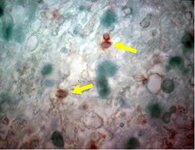

Toxoplasmose

Tomografia computadorizada: cérebro da toxoplasmose no sistema nervoso central

Do acervo de Louis M. Weiss, MD, MPH; uso autorizado